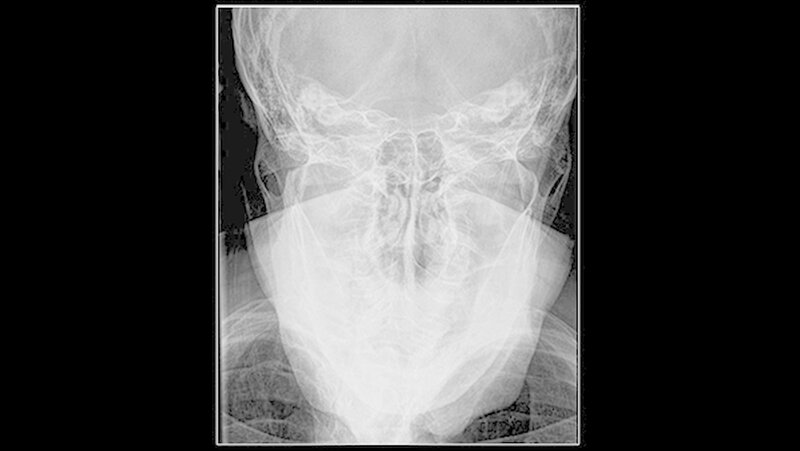

Die klinische Untersuchung zeigte eine überwärmte, schmerzhafte Schwellung präauriculär links und eine stark eingeschränkte Mundöffnung bei zahnlosem Kiefer. Das angefertigte Orthopantomogramm und die Schädelaufnahme in posterior-anteriorer Projektion gaben keinen eindeutigen Hinweis auf Pathologien im Bereich des linken Kiefergelenks, mit denen die ausgeprägten Beschwerden der Patientin hätten erklärt werden können.

Es war lediglich ein stark verschmälerter Gelenkspalt im Bereich des linken Kiefergelenks erkennbar, woraufhin eine Computertomografie des Unterkiefers durchgeführt wurde (Abbildungen 1 und 2). Dabei zeigten sich eine Deformierung des linken Kiefergelenksköpfchens mit Unregelmäßigkeiten der Kortikalis sowie eine Fremdkörpereinlagerung (freie Gelenkkörperchen) im Bereich des Gelenkspalts (Abbildungen 3 und 4).